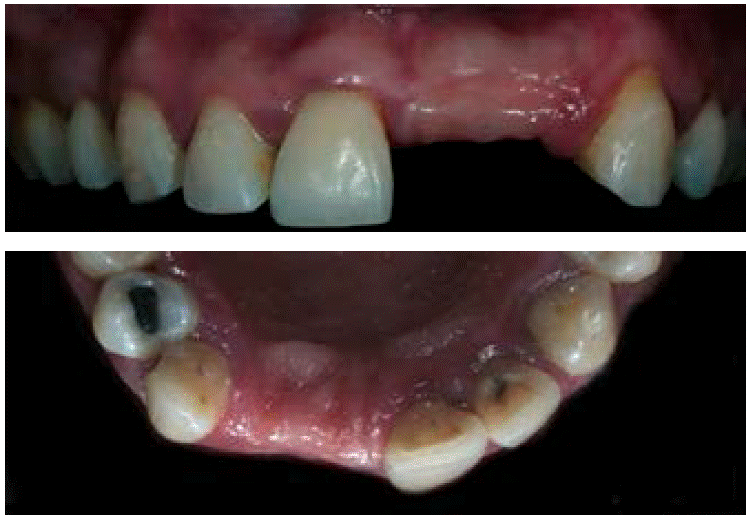

De acuerdo con la nomenclatura de la Federación Dental Internacional (FDI), la paciente tenía caries oclusales en molares y premolares, caries de cíngulo, restauraciones con amalgama, fractura en distal y caries en cíngulo del OD 23 y cuatro dientes ausentes (Figuras 3AyB). De igual forma mostró cálculo dental y tejido gingival inflamado.

Se administró anestesia local de articaína al 4% usando agujas cortas por medio de la técnica de infiltración. Se bloqueó el nervio alveolar superior anterior y el nervio nasopalatino. Posteriormente se realizó una incisión de incisivo lateral superior derecho a canino superior izquierdo de forma trapezoidal con preservación de papilas, para lo que se empleó un mango de bisturí 3 Bard Parker y una hoja de bisturí número 15C. El desprendimiento de colgajo mucoperióstico se efectuó con una la legra Prichard (Figura 6).

Se realizó un curetaje en la zona receptora, eliminando tejido de granulación con el fin de tener un nicho receptor limpio y un raspado radicular de los órganos dentales adyacentes. Se probó la lámina ósea fina de 25 × 35 mm y se recortó para adaptarse a la zona receptora (Figura 7). Se cribó el tejido óseo en la superficie vestibular del defecto con motor quirúrgico y contrángulo recto con fresa de carburo de bola del número 2 y se irrigó con suero fisiológico. El xenoinjerto Gen-Os se preparó con suero fisiológico estéril en un godete metálico estéril y fue llevado a la zona del defecto óseo (Figura 8). Una vez rellenado el defecto óseo, se liberó el colgajo hasta que llegara al tercio incisal de los órganos dentarios 12, 11 y 23. A continuación, se hidrato la lámina ósea durante aproximadamente cinco minutos en solución fisiológica hasta obtener la consistencia de plasticidad deseada. Fue adaptada en la zona receptora (Figura 9) y fijada e inmovilizada con sutura de aguja triangular no traumática Vicryl 4’0s. Se realizó la síntesis de los tejidos suturando con Nylon 4’0s empleando la técnica de colchonero vertical y algunos puntos de sutura simples. También se hizo un lavado con suero fisiológico y se limpió la zona quirúrgica con gasas estériles. Se ajustaron provisionales de tal manera que los pónticos no contactaran con la zona en regeneración.